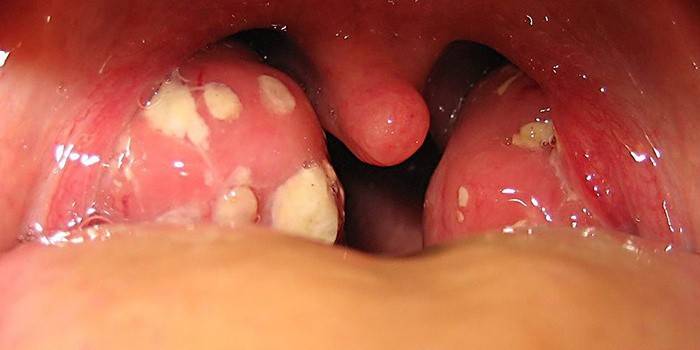

Коли ви відвідуєте терапевта під час застуди або грипу, він завжди просить вас відкрити широко рота. Так він оглядає порожнину і слизову горла, що може вказати на наявність збільшених мигдалин. Запалення гланд ще називають тонзилітом, який з’являється на увазі ускладнення після ангіни. При виявленні ознак цього захворювання пацієнтові відразу призначається лікування, яке передбачає полоскання, прийом ліків і регулярний огляд фахівцем.

Тонзиліт, або запалені гланди, має свої певні ознаки, які дуже схожі на симптоми ангіни. З ним ви зможете самостійно визначити наявність запалень в гландах:

- гостра форма ангіни;

- білий наліт на язиці;

- сильно болить горло при ковтанні;

- мігрень;

- висока температура;

- опухли лімфовузли в області шиї;

- запах з рота;

- втрата голосу.